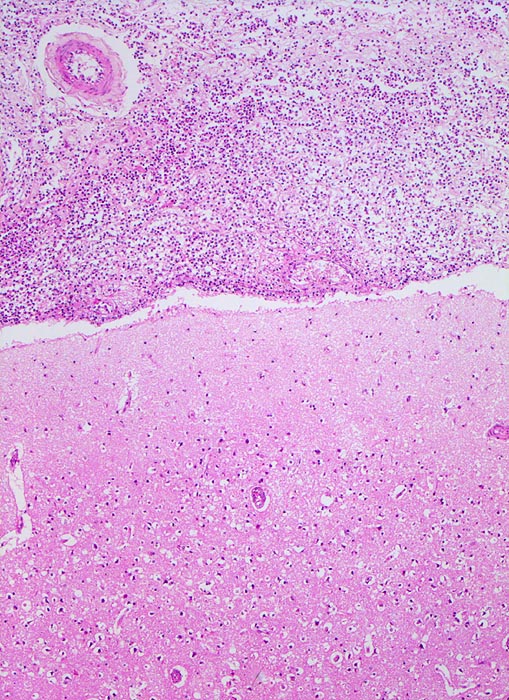

Zytologisch finden sich mehr als 90% neutrophile Granulozyten, ausserdem Fibrin, Makrophagen, degenerierende Zellen, Zelldetritus und manchmal Mikroorganismen. Nach Beginn der Antibiotikatherapie kommt es zu einem raschen Abfall der Zellzahl. Die neutrophilen Granulozyten degenerieren und aktivierte Monozyten beherrschen das Zellbild. Plasmozytoide Lymphozyten und Plasmazellen können dazukommen. In der Reparationsphase verschwinden die Granulozyten, die Anzahl Plasmazellen verringert sich, die Makrophagen sind degeneriert und haben vakuolisiertes Zytoplasma.